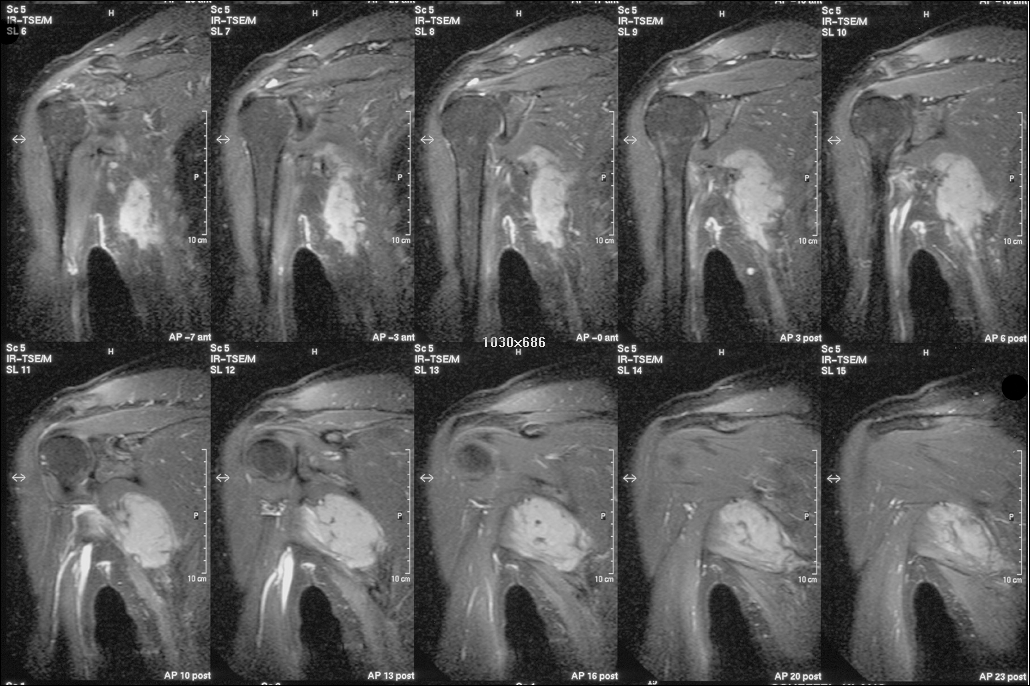

Desmoid fibromatosis is an extremely rare disease, which is known since the 19th Century [2], [28], [30], [34], [40]. Synonymous terms are: desmoid tumor, aggressive fibromatosis, desmoid-type fibromatosis, musculoaponeurotic fibromatosis [6], [12], [22], [26], [27]. It is a neoplasm of connective tissue, which arises from musculoaponeurotic structures. It is locally aggressive and infiltrates the surrounding tissue (Figure 1 [Fig. 1]).

Figure 1: Desmoid fibromatosis of the shoulder and axillary region with local aggressive infiltration (Courtesy of the Department of Radiology of the Leipzig University)

The aim of this classification was to achieve standardization and to facilitate the development of therapeutic guidelines. The first manifestation of desmoid fibromatosis is very diverse. It is reported in literature that patients usually manifest with a painless extraabdominal swelling. Intra-abdominal desmoid fibromatoses can be occult and remain completely asymptomatic over a long period of time [12], [15], [36], [41], [42]. However desmoid fibromatoses may first manifest [4], [35], [39] by pain. Depending on their localisation and extent, they can cause considerable disability and morbidity [1], [5], [9], [14], [24]. MRI (Figure 1 [Fig. 1]) is of crucial importance and is considered as the gold standard in the diagnosis [1], [14], [24], [32].